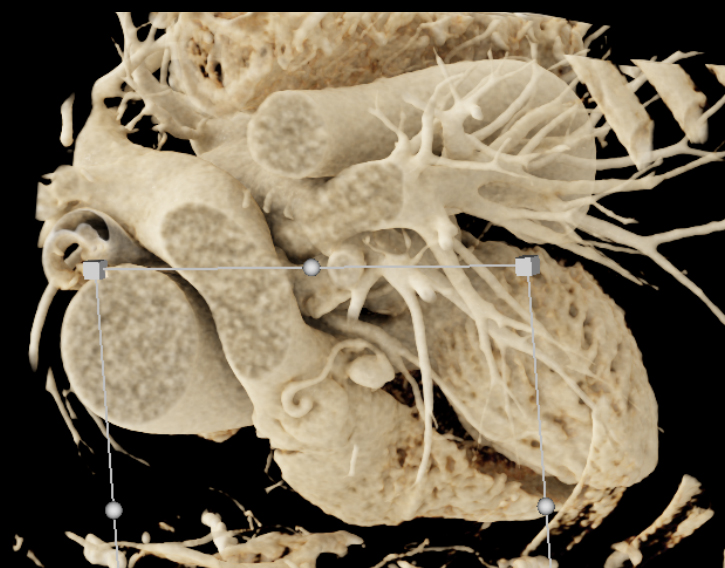

8) In this 50ish year old with chest pain the best dx is?

coronary artery plaque

aberrant origin of the RCA

aneurysm of the LAD

pulmonary embolism